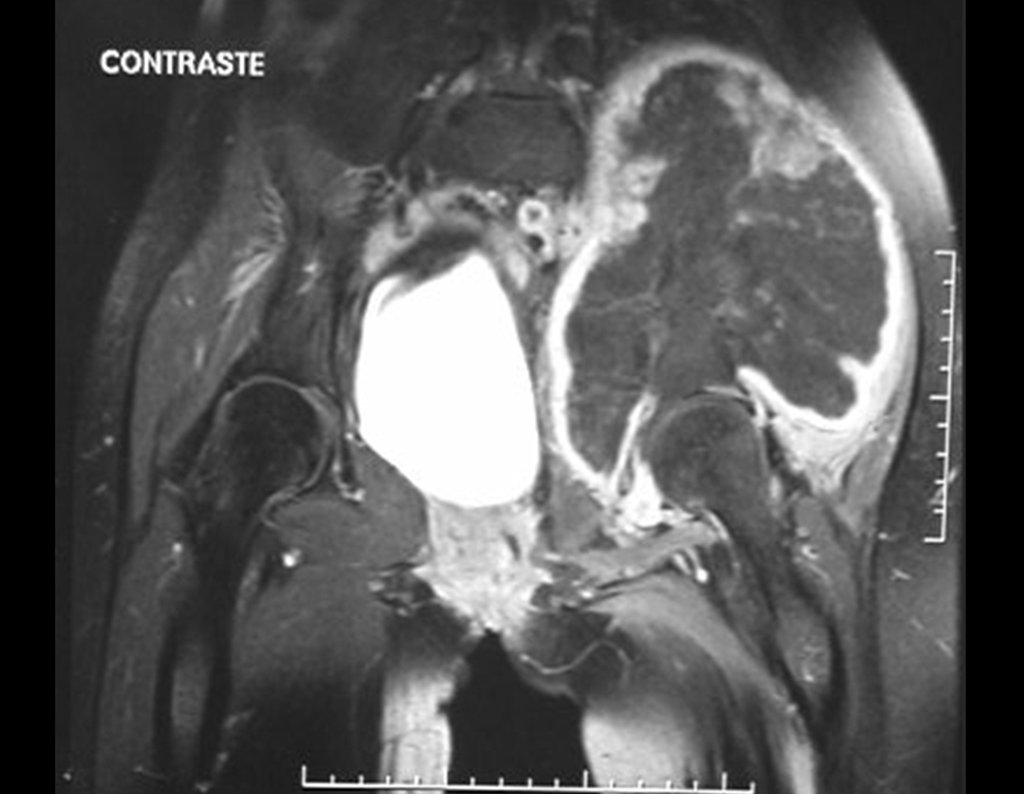

Condrosarcoma de pelvis – Pelvectomía interna total. Paciente femenina de 19 años que consulta por malestar y aumento de volumen en pelvis izquierda. Clínicamente se presentó dolor leve a la palpación del ala ilíaca, palpándose una tumoración dura y adherente. Respondido el 18 de diciembre de 2002, con los siguientes exámenes de imagen: 13/11/1983 18/12/2002.